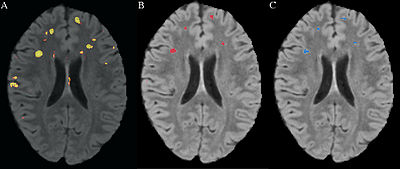

We obtained gray matter, white matter, CSF, and lesion maps for each subject based on T1-weighted, T2-weighted, and FLAIR images. Ultimately, the NA-MIC Kit will provide a workflow for individual and group analysis of lesions. It will be implemented as a set of Slicer3 modules that can be used interactively within the Slicer3 application as well as in batch on a computing cluster using BatchMake.

- Scully M, Anderson B, Lane T, Gasparovic C, Magnotta V, Sibbitt W, Roldan C, Kikinis R and Bockholt HJ (2010) An automated method for segmenting white matter lesions through multi-level morphometric feature classification with application to lupus. Front. Hum. Neurosci. 4:27. doi:10.3389/fnhum.2010.00027. Available here

- Scully, M., Lane, T., Gasparovic, C., Magnotta, V., Sibbitt, W., Roldan,C. , Kikinis, R., Bockholt, H. J. An Automated Method For Longitudinal Analysis of White Matter Lesions in Lupus (in preparation for submission).